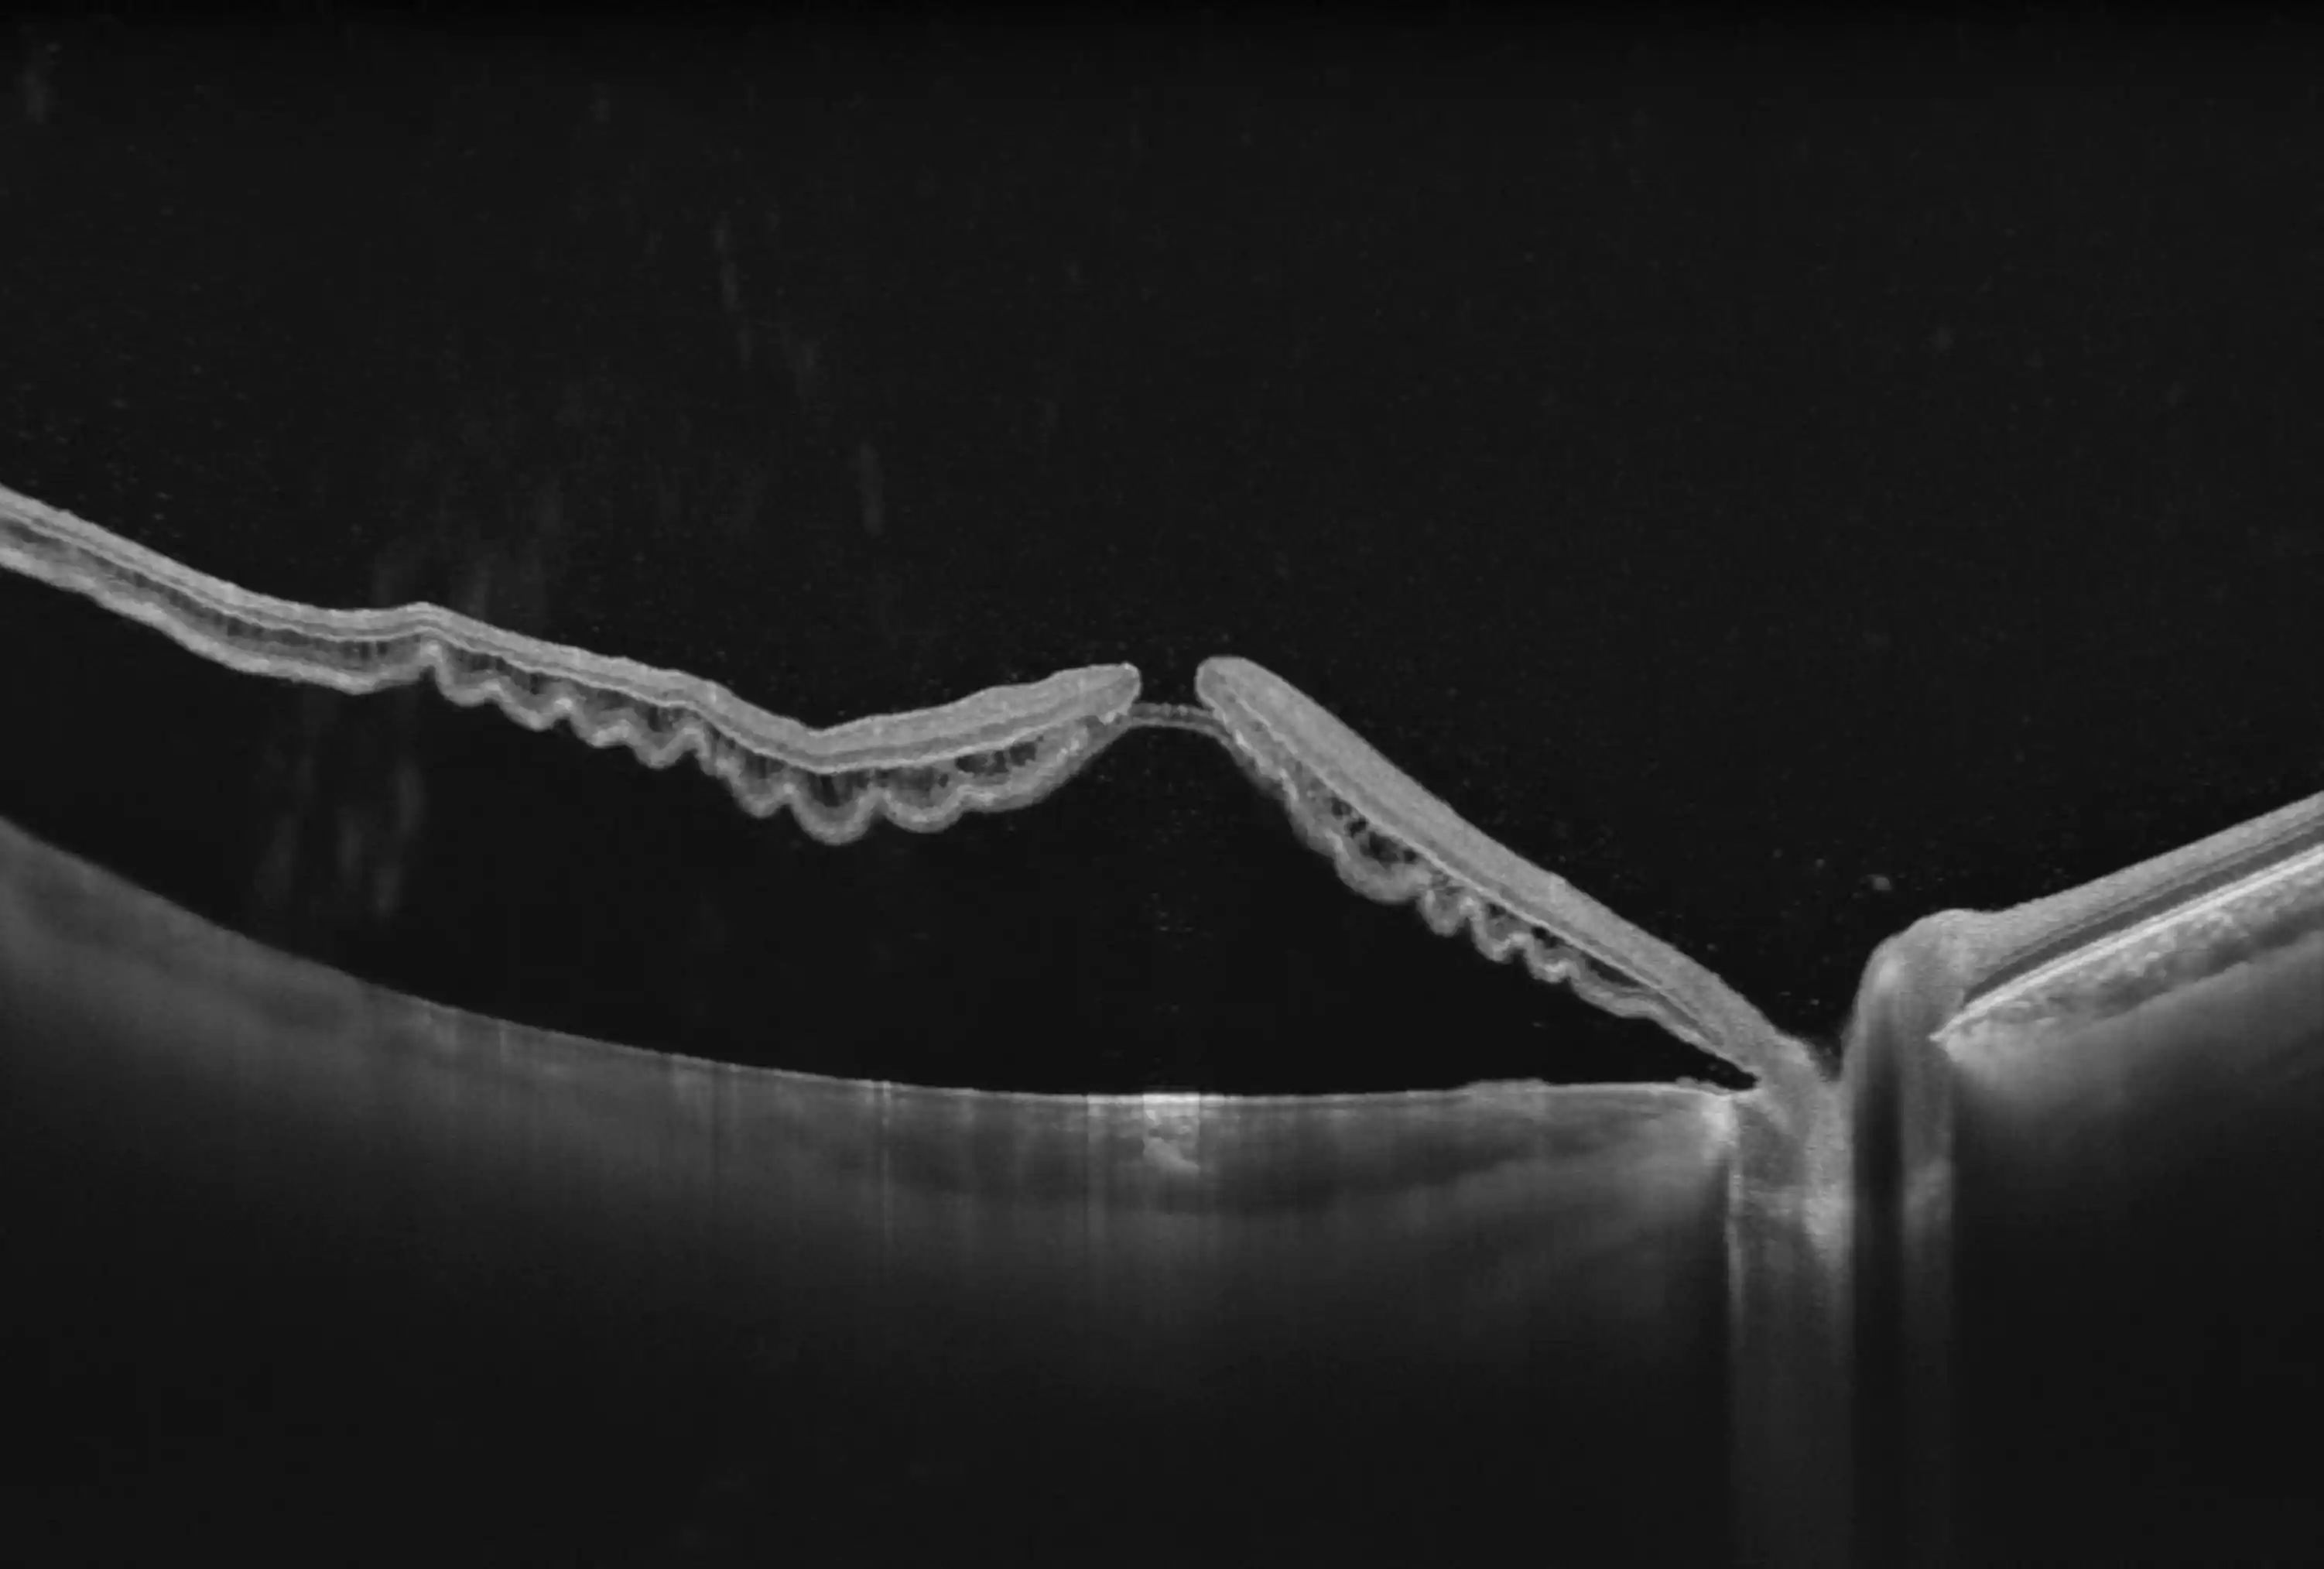

Szczegółowa analiza

Oferuje wysoką rozdzielczość osiową optyczną ≤6 µm oraz zaawansowany system Eye tracking 60 Hz (LSO), który stabilizuje obraz mimo ruchów pacjenta, co przekłada się na wiarygodne i powtarzalne wyniki.

Wykorzystuje zaawansowane algorytmy sztucznej inteligencji do automatycznej segmentacji warstw siatkówki i naczyniówki, pomiary ilościowe segmentu przedniego i tylnego, analizę jaskry oraz kwantyfikację przepływu krwi, a także rekonstrukcje 3D

Zaawansowane Algorytmy AI

Wsparcie dla automatycznej segmentacji warstw siatkówki, nawet w przypadkach patologicznych

Analiza Segmentu Przedniego (AS)

Pomiary ilościowe, parametry panoramiczne, mapa grubości rogówki, głębokość komory przedniej i kąt przesączania